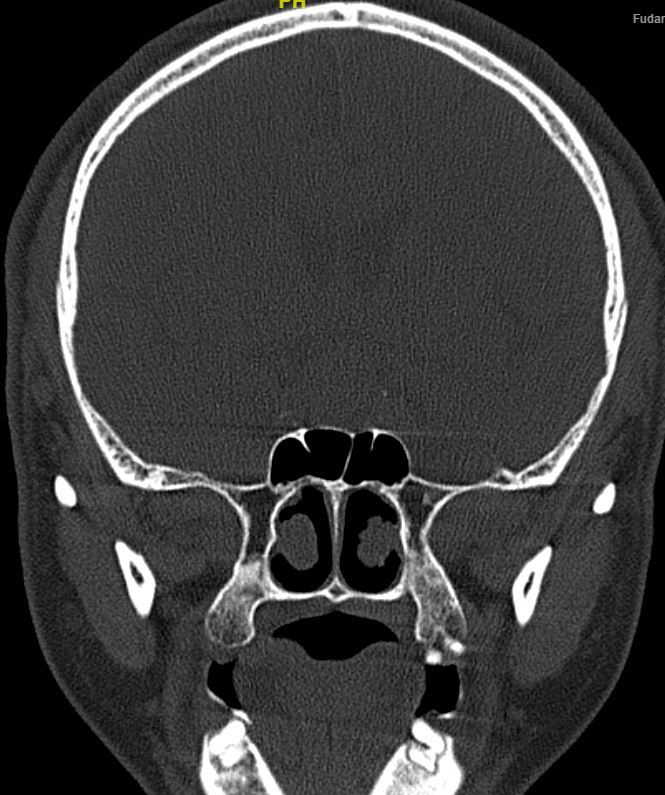

冠状位骨窗